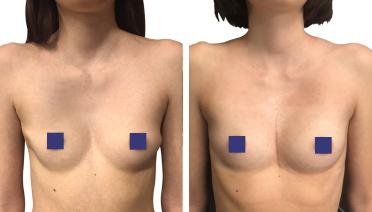

La tecnica di impianto su misura è una tecnica chirurgica minore che consiste nel riempire la concavità creata dal Pectus con un impianto personalizzato. Si tratta di un intervento rapido, a basso rischio, con un risultato immediato e una breve convalescenza.

In questa pagina, troverà i risultati di questa operazione a seconda del tipo di Pectus : mediale, asimmetrico, più o meno profondo o lungo.

Tipo 1 : Mediano, profondo e simmetrico,